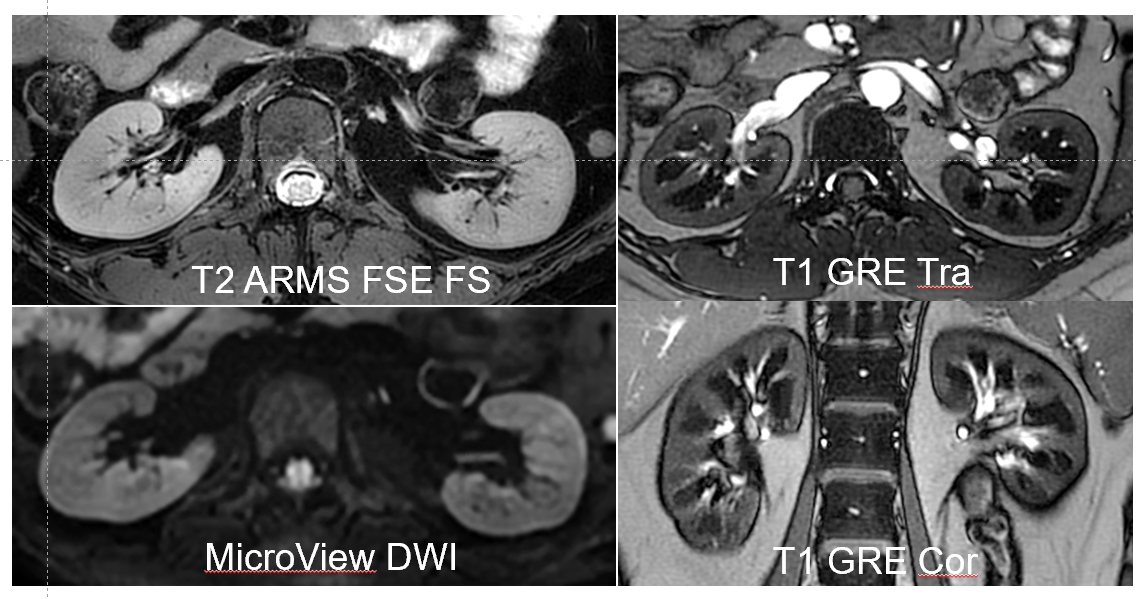

对肾脏解剖结构、血流灌注、氧合状态、微结构及功能的全面评估,用于早期发现肾功能损伤、鉴别肿瘤良恶性、监测移植肾状态,辅助诊断肾病、肾缺血或肾小球疾病。以下是几种关键技术的应用:

DWI(弥散加权成像):通过检测水分子扩散运动,反映组织微观结构变化。在肾脏中,DWI可用于评估急性肾损伤、肿瘤良恶性鉴别及纤维化程度。

MRI相较于CT,首先是无电离辐射,能清晰区分肾脏皮质、髓质、集合系统及周围脂肪,对小肿瘤、囊肿、炎症的显示更加清晰,该项检查不需要造影剂,对肾功能不全的患者无风险,总的来说在肾功能评估、早期病变检出、血管成像及长期随访中优势明显,尤其适合肾功能不全、儿童、孕妇及复杂肾病患者。